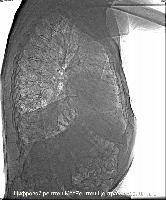

Магнитно-резонансная томография (МРТ):один из самых эффективных методов диагностики заболеваний